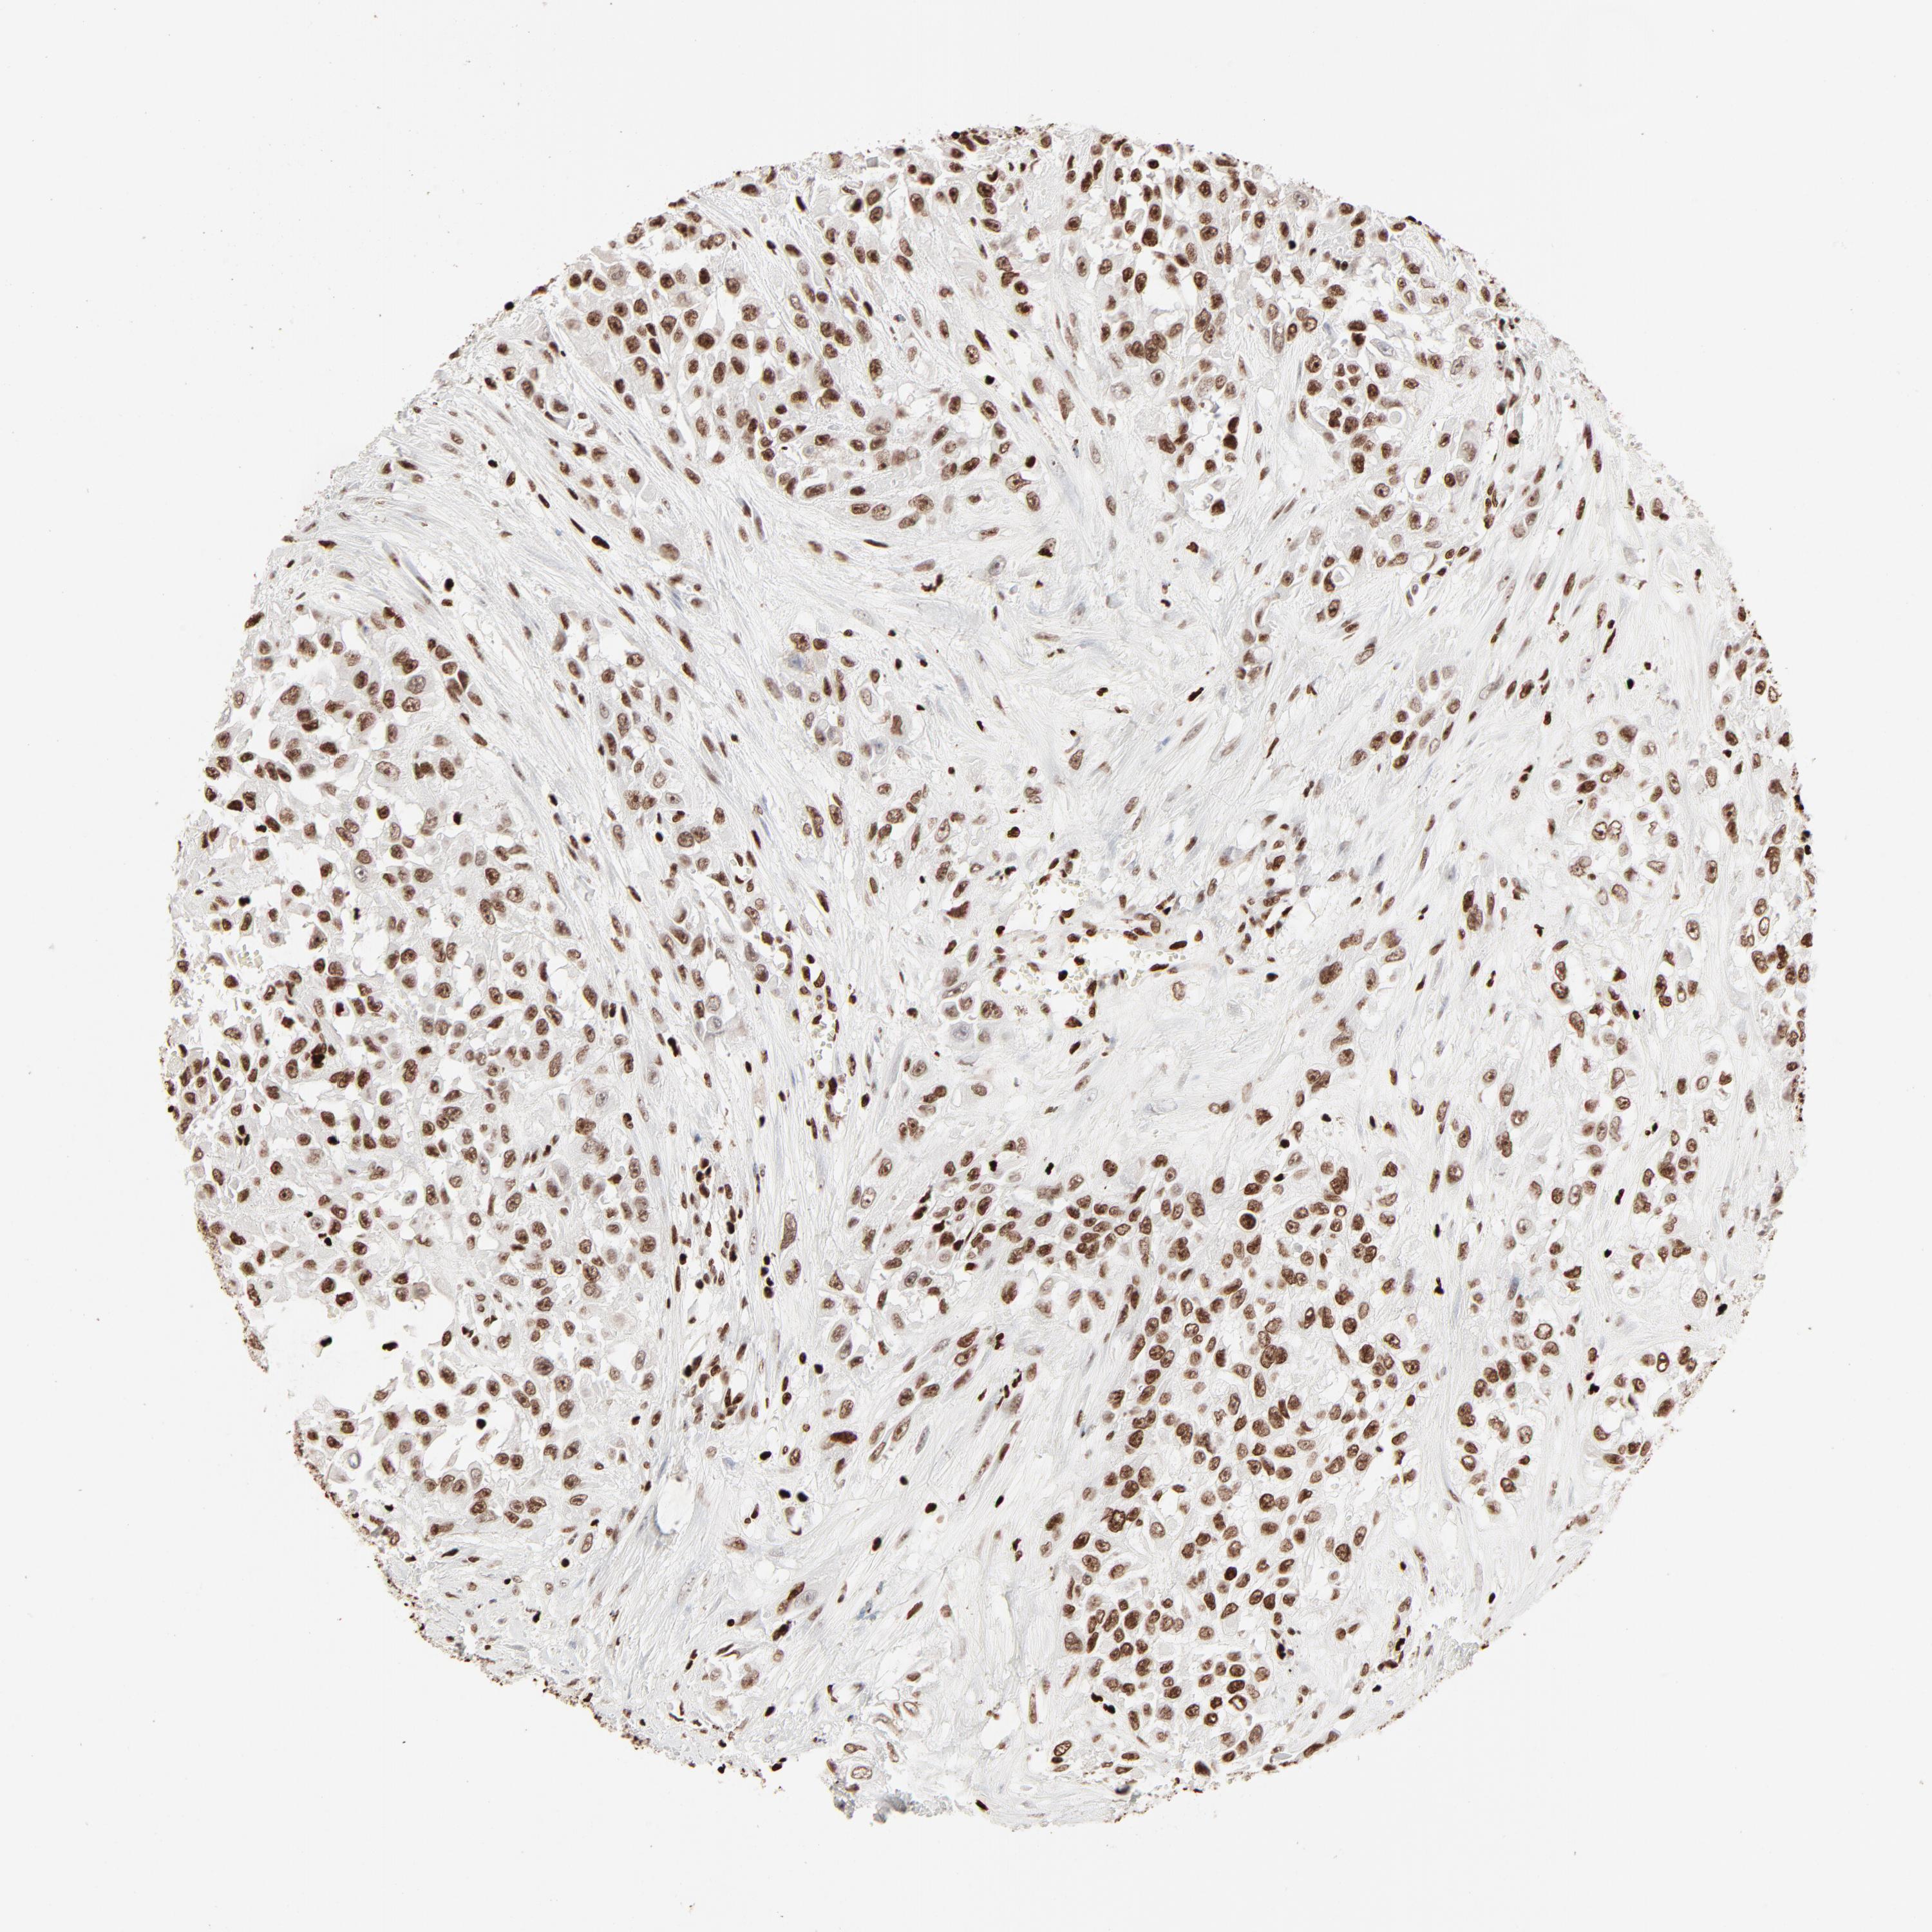

UROTHELIAL CANCER - Protein expressioni

A mouse-over function shows sample information and annotation data. Click on an image to view it in a full screen mode. Samples can be filtered based on level of antibody staining by selecting one or several of the following categories: high, medium, low and not detected. The assay and annotation is described here.

Note that samples used for immunohistochemistry by the Human Protein Atlas do not correspond to samples in the TCGA dataset.

Antibody stainingi

Antibody staining in the annotated cell types in the current human tissue is reported as not detected, low, medium, or high, based on conventional immunohistochemistry profiling in selected tissues. This score is based on the combination of the staining intensity and fraction of stained cells.

Each image is clickable and will lead to virtual microscopy that enables deeper exploration of all samples and also displays staining intensity scores, fraction scores and subcellular localization as well as patient and tissue information for each sample.

Antibody HPA003506

Antibody CAB005873

Staining

High

Medium

Low

Not detected

Intensity

Strong

Moderate

Weak

Negative

Quantity

>75%

75%-25%

<25%

None

Location

Nuclear

Cytoplasmic/membranous

Cytoplasmic/membranous,nuclear

Urothelial carcinoma, High grade

Urothelial carcinoma, Low grade